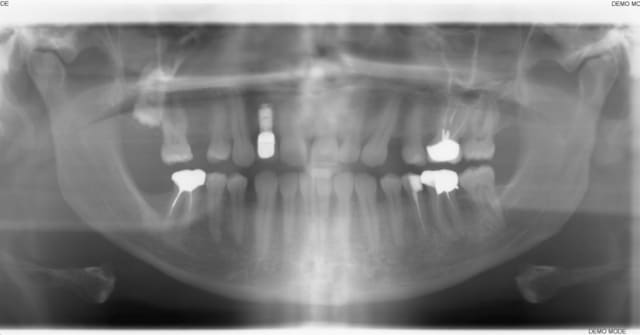

voila un patient qui se présente en consult car il veut remplacer la 24 absente. sur la pano, l'apex de la 23 empêche de venir placer un implant. je lui ai proposé de consulter un ortho pour redresser l'axe de la 23, mais je n'ai aucune idée, quand à la possibilité et au temps que peut prendre ce genre de traitement.

C'est un mouvement assez facile à faire mais qui demande un peu de temps car la racine est volumineuse, un an de traitement me paraît raisonnable

A priori c'est surtout la position de l'apex qu'il faut contrôler. Le plus efficace serait sans doute de gérer ça avec des mini vis (+/- plaque) et des sectionnels. Dans ce cas pas besoin de coller toute l'arcade. Stratégie à choisir en fonction des objectifs du ttt (id est juste la 24 à gérer ≠ ttt global).